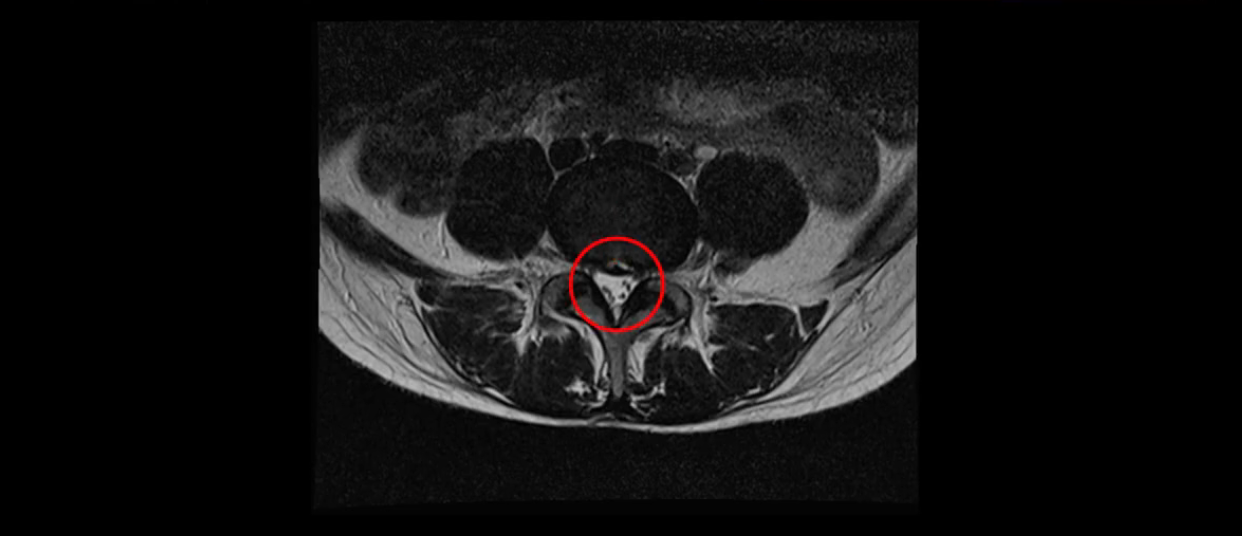

5번 1번은 디스크 탈출이 가운데 쪽으로 살짝 있습니다.

또한 양쪽 신경 가지가 빠져나가는 추간공은 매우 넓은 상태입니다.

중요한 것은 이 정도 경미한 탈출과 협착으로는 양쪽 다리가 저리고 아플 수가 없습니다.

그리고 만약에 이 디스크가 급성으로 찢어진 것이라면 아주 심한 디스크성 통증이 있겠죠. 기침이나 재채기를 하면 심하게 아프고 허리를 조금만 구부려도 아주 날카로운 통증들이 생길 겁니다. 그런데 이분은 이런 증상이 전혀 아닙니다. 디스크의 돌출 정도와 협착이 전혀 심하지 않기 때문에 이분이 가지고 계신 양쪽 다리 저림, 특히 이분은 누워있을 때도 양쪽 다리가 저리다고 하는데, 디스크 때문에 그런 증상은 생길 수가 없습니다. 또 이 디스크는 오래된 디스크, 이미 찢어진 섬유륜이 아문 디스크이고, 그러니까 이분은 기침이나 재채기를 못하는 증상이 없는 거죠. 그 다음에 허리를 구부릴 때 뻐근한 증상은 있지만 아주 날카로운 통증은 없습니다.

이분 MRI를 보시면 퇴행성디스크가 있고 약간의 협착이 있지만 이 정도의 퇴행성디스크와 협착으로는 신경이 눌려서 양쪽 다리가 저리고 아픈 증상이 나올 수가 없습니다. 그래서 MRI와 이 환자분의 다리 증상이 매치가 안 된다고 하는 의사들이 많은 겁니다.